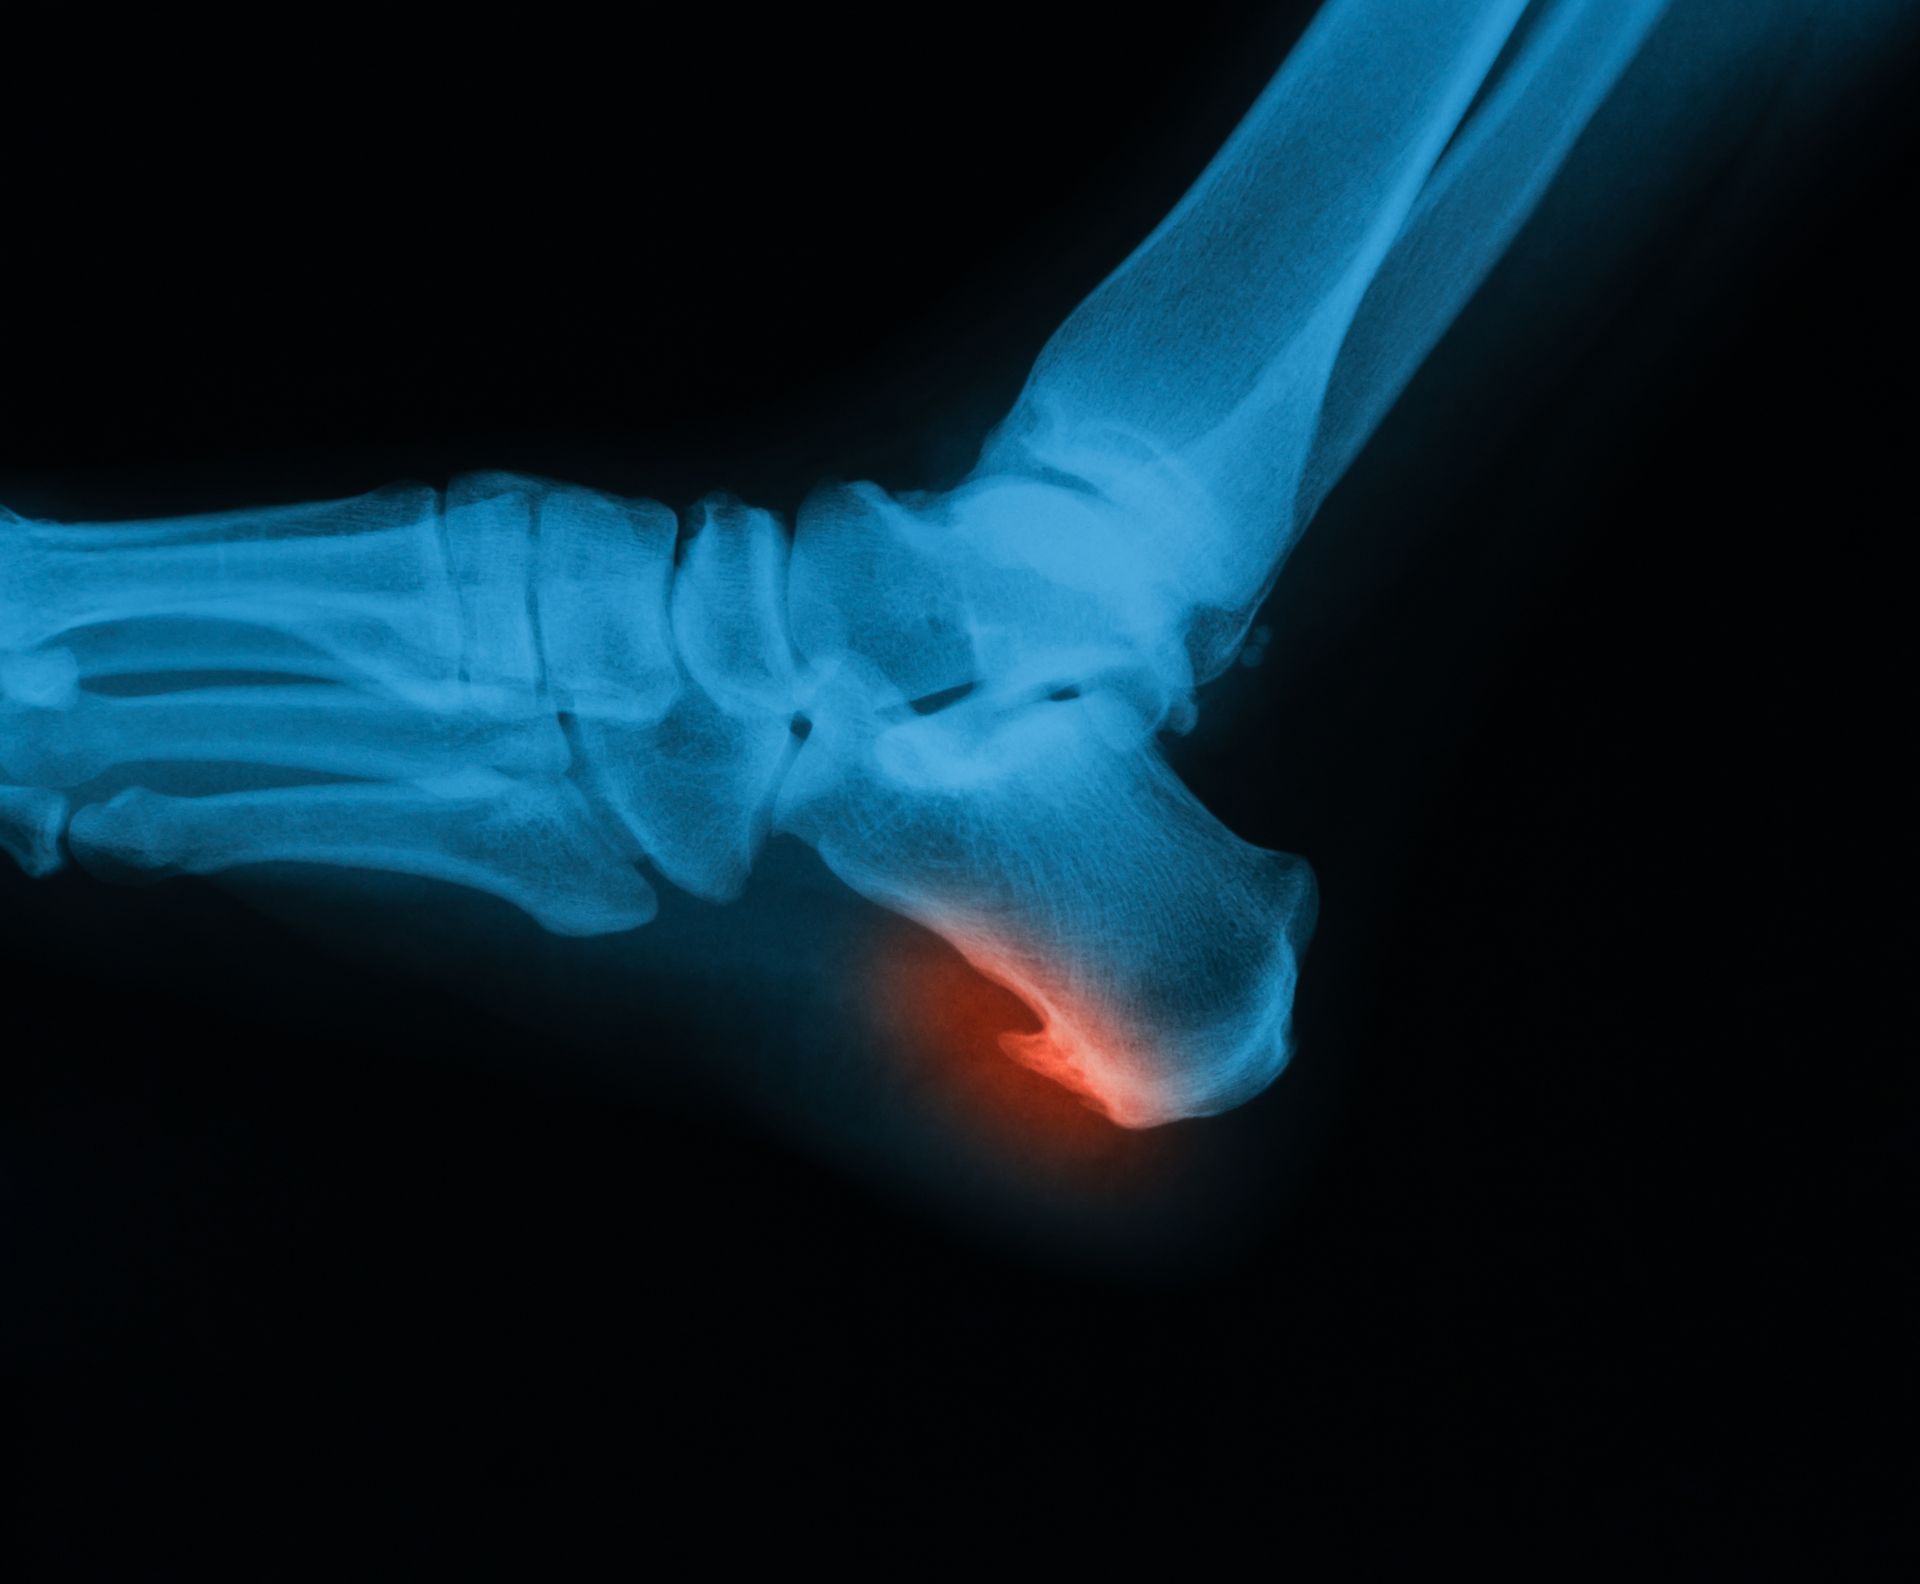

Podiatric medicine focuses on diagnosing and treating conditions of the foot, ankle, and lower leg. Podiatrists provide comprehensive care through exams, accurate diagnoses, and effective treatments. They can perform surgery when needed, prescribe medications, recommend therapeutic exercises, fit custom orthotics, and guide patients on footwear, prevention, and lifestyle choices to support long-term foot and ankle health.